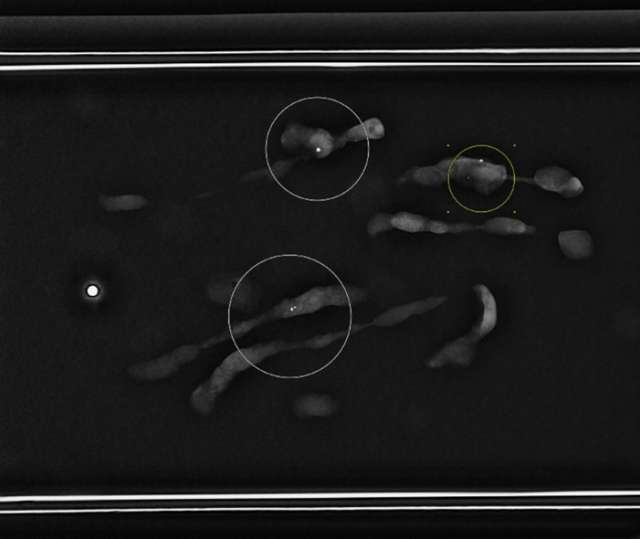

- Radiologist confirms adequate tissue sampling (Figure 5).

Figure 5. Specimen radiograph demonstrates multiple tissue samples containing calcifications (circled).